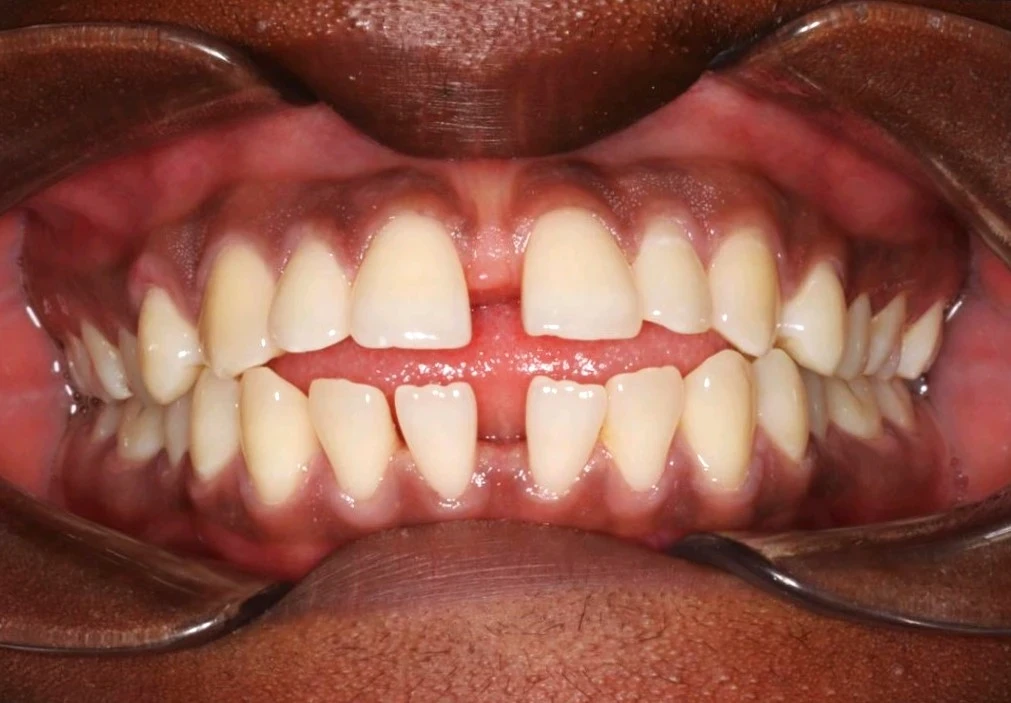

Spécialité médicale à part entière, l’orthodontie se consacre à l’étude et à l’art de corriger la forme, la position et le fonctionnement des arcades dentaires. Destinés aux enfants dès l’âge de 6 ans, aux adolescents, ainsi qu’aux adultes, les traitements d’orthodontie s’inscrivent dans une démarche de qualité, tant esthétique que fonctionnelle, mais aussi de prévention. Ils visent à prévenir les dysharmonies des mâchoires et les malpositions dentaires susceptibles d’avoir des conséquences néfastes sur :

L'harmonie du sourire est souvent la première source de motivation pour nos patients. Pour autant, l’alignement des dents entraîne également d’autres bienfaits. En effet, en plus de permettre le bon déroulement du vieillissement dentaire, la qualité de l’occlusion favorise l’efficacité du brossage des dents, tout en luttant contre le déchaussement gingival.

Spécialité médicale à part entière, l’orthodontie se consacre à l’étude et à l’art de corriger la forme, la position et le fonctionnement des arcades dentaires. Destinés aux enfants dès l’âge de 6 ans, aux adolescents, ainsi qu’aux adultes, les traitements d’orthodontie s’inscrivent dans une démarche de qualité, tant esthétique que fonctionnelle, mais aussi de prévention. Ils visent à prévenir les dysharmonies des mâchoires et les malpositions dentaires.